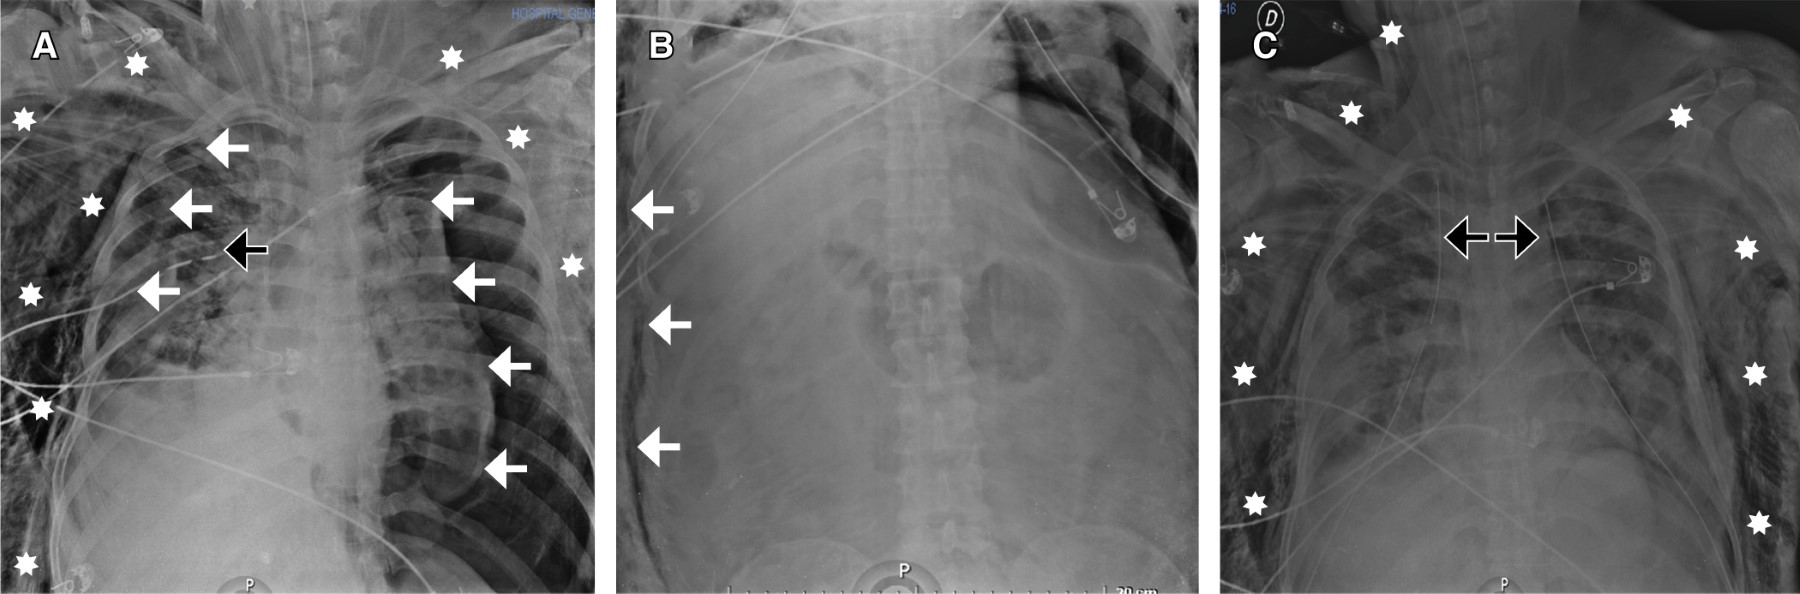

Extensive subcutaneous emphysema

Subcutaneous emphysema is common complication self-limited complication of tube thoracostomy. Any subcutaneous emphysema on positive pressure ventilation, causing palpable cutaneous tension, palpebral closure, dysphagia, and dysphonia or associated with pneumoperitoneum, airway compromise, "tension phenomenon" and respiratory failure is labelled extensive subcutaneous emphysema.

Figure 2

Figure 3

Figure 4